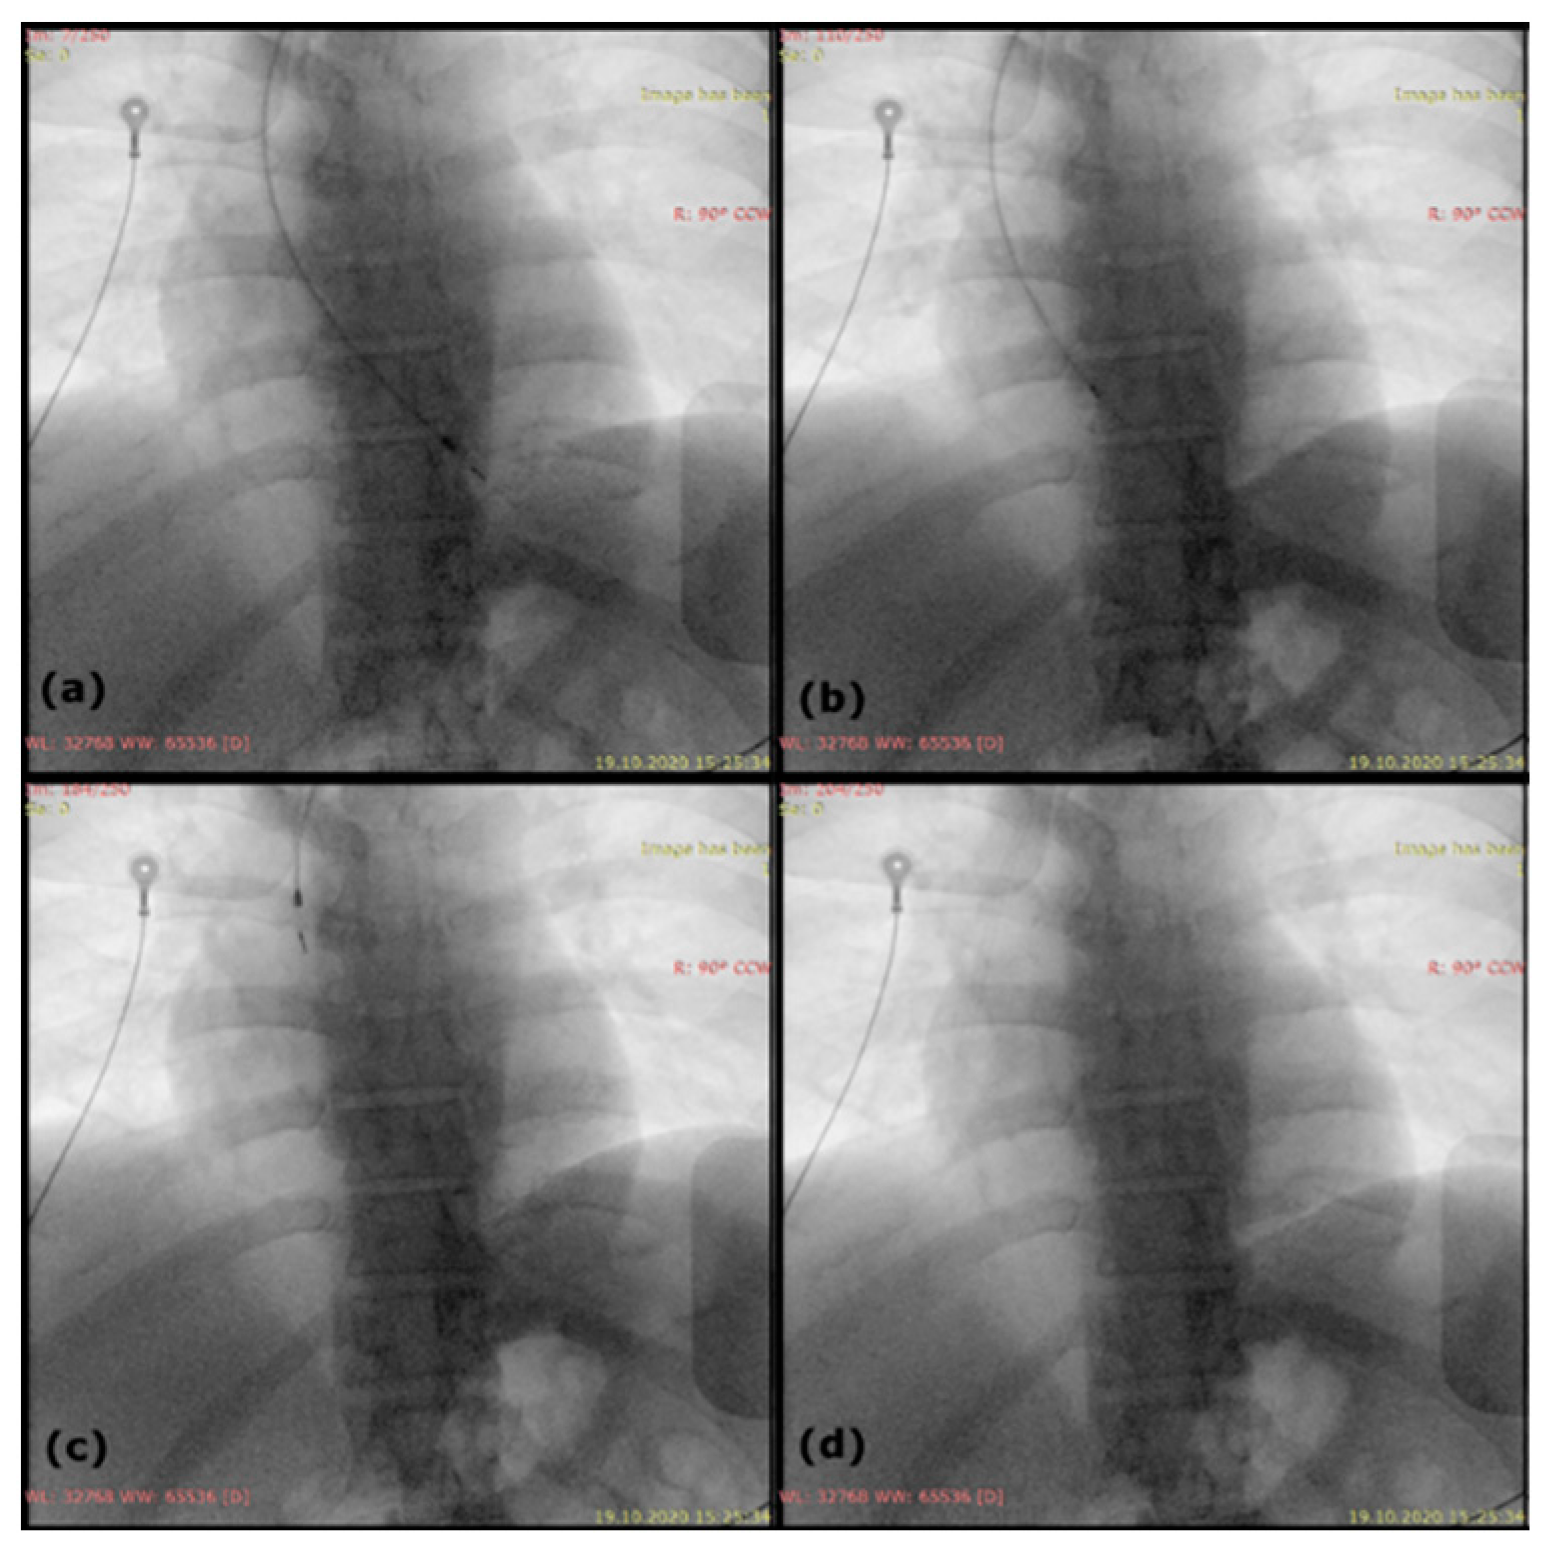

2. Case Report